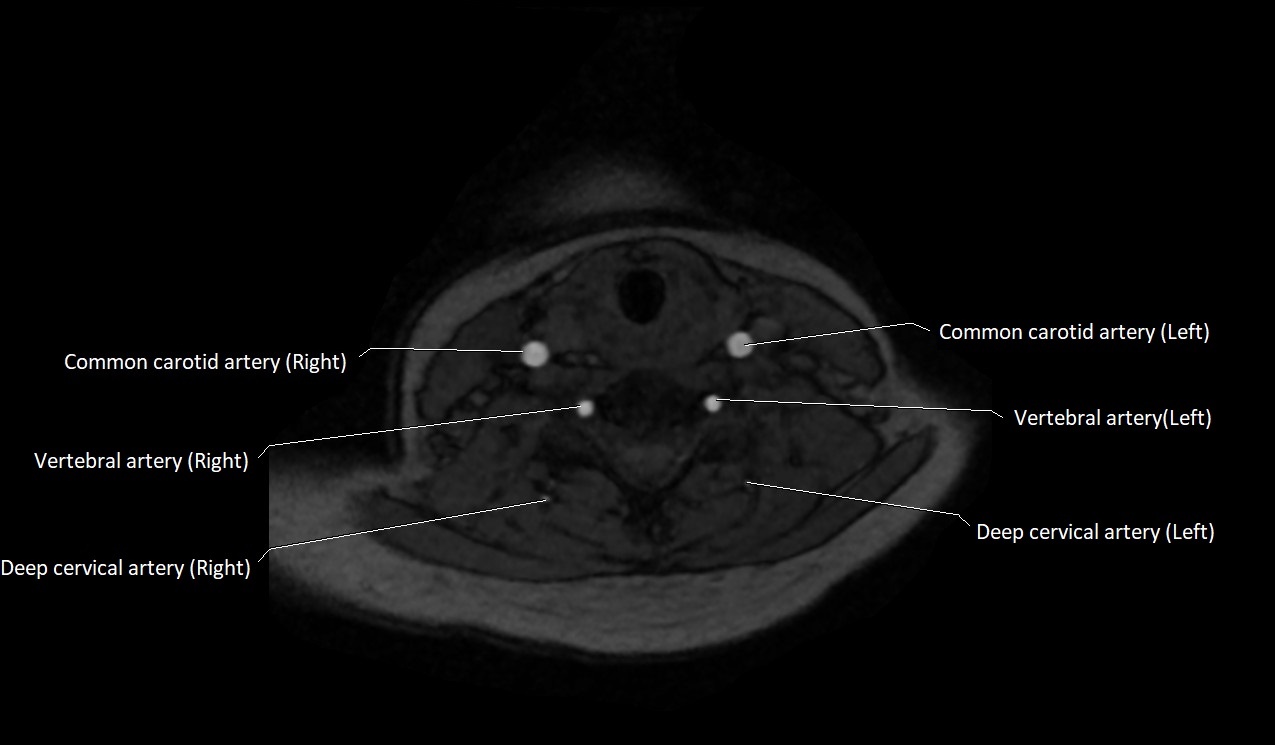

CT image

image